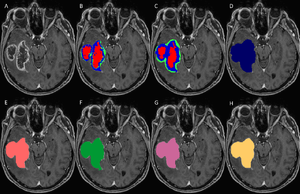

Publication: PLoS One. 2016 Nov 2;11(11):e0165302. PMID: 27806121 | PDF Authors: Porz N, Habegger S, Meier R, Verma R, Jilch A, Fichtner J, Knecht U, Radina C, Schucht P, Beck J, Raabe A, Slotboom J, Reyes M, Wiest R. Institution: Support Center for Advanced Neuroimaging, Institute for Diagnostic and Interventional Neuroradiology, University Hospital and University of Bern, Bern, Switzerland. Background/Purpose: Comparison of a fully-automated segmentation method that uses compartmental volume information to a semi-automatic user-guided and FDA-approved segmentation technique. METHODS: Nineteen patients with a recently diagnosed and histologically confirmed glioblastoma (GBM) were included and MR images were acquired with a 1.5 T MR scanner. Manual segmentation for volumetric analyses was performed using the open source software 3D Slicer version 4.2.2.3. Semi-automatic segmentation was done by four independent neurosurgeons and neuroradiologists using the computer-assisted segmentation tool SmartBrush® (referred to as SB), a semi-automatic user-guided and FDA-approved tumor-outlining program that uses contour expansion. Fully automatic segmentations were performed with the Brain Tumor Image Analysis (BraTumIA, referred to as BT) software. We compared manual (ground truth, referred to as GT), computer-assisted (SB) and fully-automated (BT) segmentations with regard to: (1) products of two maximum diameters for 2D measurements, (2) the Dice coefficient, (3) the positive predictive value, (4) the sensitivity and (5) the volume error. RESULTS: Segmentations by the four expert raters resulted in a mean Dice coefficient between 0.72 and 0.77 using SB. BT achieved a mean Dice coefficient of 0.68. Significant differences were found for intermodal (BT vs. SB) and for intramodal (four SB expert raters) performances. The BT and SB segmentations of the contrast-enhancing volumes achieved a high correlation with the GT. Pearson correlation was 0.8 for BT; however, there were a few discrepancies between raters (BT and SB 1 only). Additional non-enhancing tumor tissue extending the SB volumes was found with BT in 16/19 cases. The clinically motivated sum of products of diameters measure (SPD) revealed neither significant intermodal nor intramodal variations. The analysis time for the four expert raters was faster (1 minute and 47 seconds to 3 minutes and 39 seconds) than with BT (5 minutes). CONCLUSION: BT and SB provide comparable segmentation results in a clinical setting. SB provided similar SPD measures to BT and GT, but differed in the volume analysis in one of the four clinical raters. A major strength of BT may its independence from human interactions, it can thus be employed to handle large datasets and to associate tumor volumes with clinical and/or molecular datasets ("-omics") as well as for clinical analyses of brain tumor compartment volumes as baseline outcome parameters. Due to its multi-compartment segmentation it may provide information about GBM subcompartment compositions that may be subjected to clinical studies to investigate the delineation of the target volumes for adjuvant therapies in the future. |

Set of MRI sequences used in this study for manual, automatic, and semi-automatic tumor volumetry. Original T1-weighted post-contrast MRI slice (A), manual subcompartmental segmentation into non-enhancing tumor (green), enhancing tumor (blue), and necrotic tissue (red) (B). BT subcompartmental segmentation into non-enhancing tumor (green), enhancing tumor (blue) and necrotic tissue (red) (C). BT core tumor segmentation (dark blue, D), SB1 core tumor segmentation (light red, E), SB2 core tumor segmentation (green, F), SB3 core tumor segmentation (purple, G) and SB4 core tumor segmentation (yellow, H). |